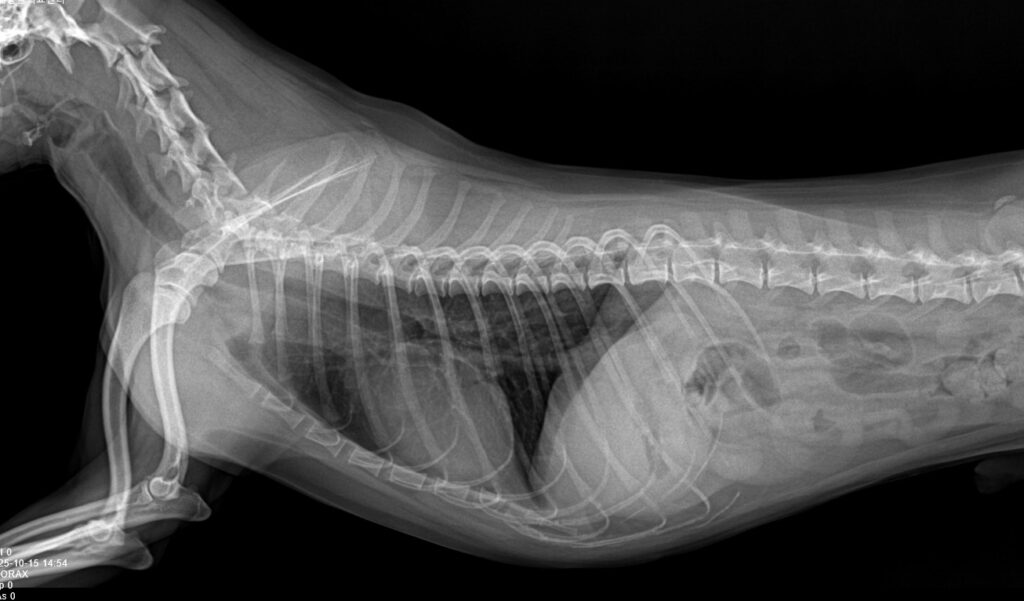

수술을 결정하기에 앞서 마취 전 혈액검사와 흉부 엑스레이 촬영을 통해 전신 상태를 먼저 평가했습니다. 간·신장 수치, 혈구 수치,흉부 상태 모두에서 특이 소견은 관찰되지 않았으며, 전신 마취 및 수술을 진행하기에 무리가 없는 상태로 판단되었습니다. 이 단계는 수술 그 자체만큼이나 중요한 과정으로, 아이의 안전을 위한 필수 절차입니다.

환자 흉부 방사선 검사/ 출처: 미래동물의료센터